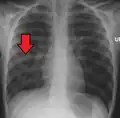

![]() | |

| Chest X-ray of a pneumonia caused by influenza and Haemophilus influenzae, with patchy consolidations, mainly in the right upper lobe (arrow) | |

Right middle lobe pneumonia in a child as seen on plain X-ray